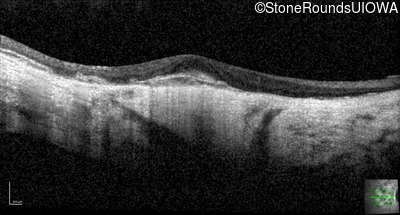

Optical Coherence Tomography - Right - 20/160 -2

Exemplar / OCT Stack

OCT Stack